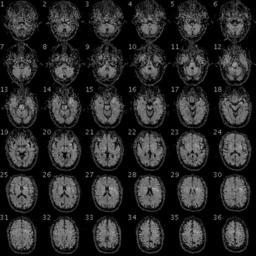

MAKE A MEME View Large Image 100325 RS88UH 11 qc.gif en fMRI of the brain/head of a PGP participant with the following data Demographic Information Date of Birth 1954-08-28 58 years old Gender Male Weight 246lbs 112kg Height 6ft 5in 195cm Blood Type O+ Race White https ...

View Original:100325 RS88UH 11 qc.gif (480x480)

Keywords: 100325 RS88UH 11 qc.gif en fMRI of the brain/head of a PGP participant with the following data Demographic Information Date of Birth 1954-08-28 58 years old Gender Male Weight 246lbs 112kg Height 6ft 5in 195cm Blood Type O+ Race White https //my personalgenomes org/profile/hu43860C Personal Genome Project https //my personalgenomes org/profile/hu43860C PGP Scientists 2010-04-29 cc-zero To the extent possible under law PersonalGenomes org has waived all copyright and related or neighboring rights to Personal Genome Project Participant Genetic and Trait Dataset This work is published from United States Magnetic resonance imaging Personal Genome Project